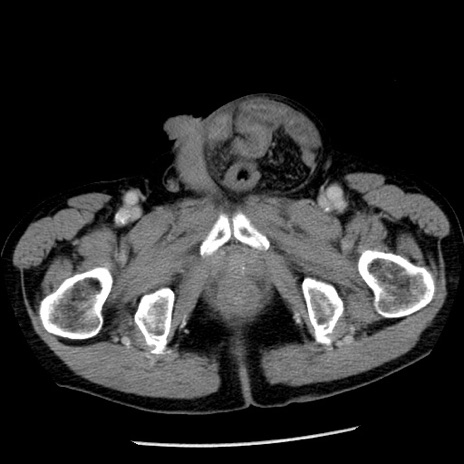

症例26(横断像)

【症例】80歳代男性

【主訴】嘔吐

【現病歴】昨晩2回嘔吐あり、今朝になっても嘔吐あり。来院。

【既往歴】胃潰瘍

【身体所見】意識清明、BT 37.6℃、BP 166/95mmHg、HR 100bpm、SpO2 97%、腹部:平坦・軟、腸蠕動音聴取良好、圧痛なし。

【データ】WBC 21900、CRP 1.46